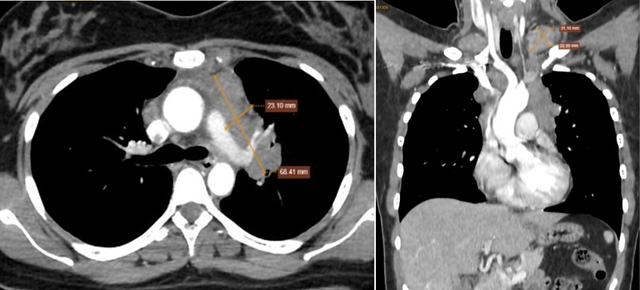

Qua thăm khám, bác sĩ ghi nhận khối ở hố thượng đòn trái kích thước khoảng 3x2 cm, mật độ chắc, di động kém. Các xét nghiệm chuyên sâu sau đó cho thấy nhiều hạch bất thường ở vùng cổ, trung thất và phổi.

Hình ảnh cho thấy nhiều hạch bất thường trung thất và nền cổ 2 bên. Ảnh: BVCC